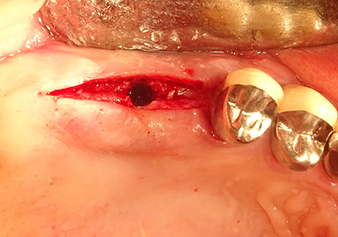

Following an intermediate check (Fig. 4) a further preparation step was performed (Fig. 5). Afterwards, the hydraulic Z35P instrument was used to lift the membrane to the desired position (Fig. 6 and 7). This was followed by further piezosurgical preparation of the implant bed, concluded with a rotary bur and shoulder milling cutter up to the implant diameter of 4.8 mm. Before the implant was inserted, the augmentation material (particle size approx. 0.8-1.6 mm) was introduced underneath the Schneiderian membrane (Fig. 8).

Implantation and prosthetic restoration

To move the augmentation material in the direction of the maxillary sinus atraumatically, the implant was inserted very slowly by hand (Fig. 9). In the process, the membrane was pushed in the cranial direction once again. After two months, the surgical site healed without irritation. Six months later, the x-ray check showed a significant increase in opacity as an indication of ossification (Fig. 10). The prosthetic restoration was carried out with a metal-ceramic crown.